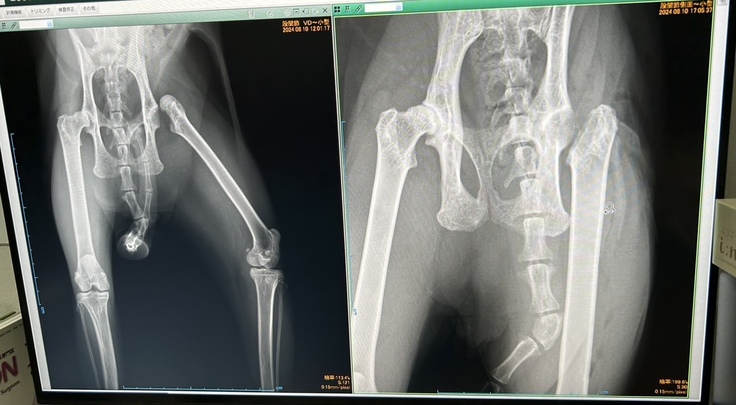

かかりつけの病院が閉まる頃だったので、その日は一晩様子を見ました。翌朝も歩き方は変わらずかかりつけへ受診、レントゲンを撮ると左股関節が脱臼していました。

先生には「麻酔をかけて整復はできるけど、腱や靱帯が伸びたり切れたり関節包が破れたりしていると思うから、整復してもその日のうちに再脱臼する可能性はある。その度に麻酔をかけて整復するよりは、骨頭を切除してしまった方が良い」と言われました。

人間のように整復して固定しても、その後安静を保つ事ができないため、外科的な治療を勧められました。かかりつけの病院の手術枠に空きがなく、別の病院を紹介していただき、その日のうちに手術、翌日退院となりました。

←術前 術後→

完全に元通りにはならないかもだけど、走ったりジャンプもできるようになると聞いていましたが、今も引きずって歩いている状態です。経過観察のため、半年に一度受診を勧められました。